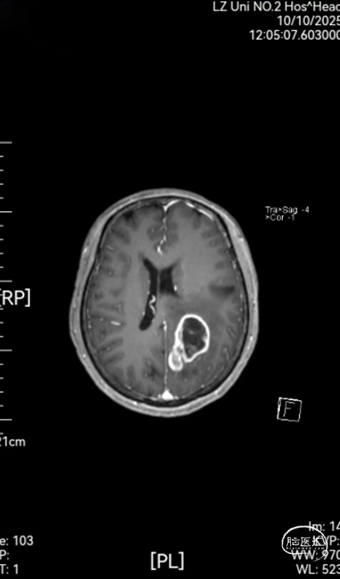

➤ 颅脑MRI平扫,增强及MRS结果:双侧大脑半球对称,灰白质比例正常,左侧顶叶见囊实性长T1长T2信号影,实性成分呈稍长T1稍长T2信号,T2-FLAIR及DWI呈稍高信号,增强后呈边缘明显环形强化,大小约29mm×48mm×46mm,周围脑实质见斑片状稍长T1稍长T2水肿信号影,左侧侧脑室轻度受压变窄;MRS示双侧海马区Cho峰明显升高,NAA峰无明显降低。双侧半卵圆中心及侧脑室旁可见散在斑片状稍长T1稍长T2信号,T2-FLAIR呈稍高信号,DWI呈等信号,边界模糊,增强后未见强化。各脑室,脑池大小形态正常,中线结构居中,幕下小脑,脑干无异常,矢状面扫描示垂体大小形态正常,强化均匀。颅脑MRA示双侧颈内动脉,大脑中动脉,大脑前动脉及大脑后动脉及其分支走行略僵硬,管壁毛糙,无明显局灶性增粗或变细。颅脑MRV示上矢状窦,直窦,窦汇,横窦及乙状窦显示良好,走行连续,未见明显增粗或狭窄。

图1:术前头颅MRI平扫,增强及MRS

➤ 诊断意见:1. 左侧顶叶占位,周围脑实质明显水肿,考虑高级别胶质瘤可能,请结合临床。2. 双侧半卵圆中心及侧脑室旁散在缺血性脑白质病变(改良Fazekas I级)。3. 颅脑动脉轻度硬化征象。4. 颅脑MRV未见明显异常。